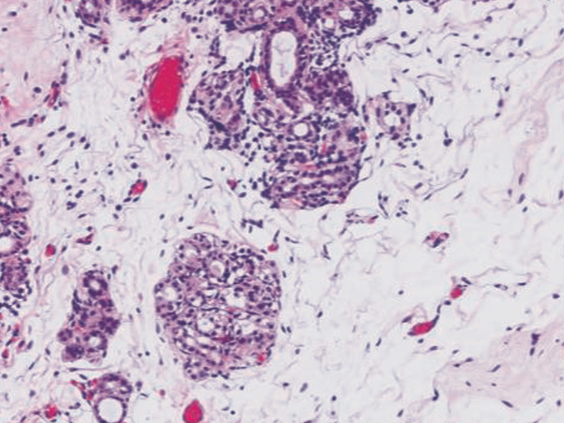

Revos Results in Excellent Tissue Morphology

The canted chamber in Revos enhances the distribution of reagent, reduces tissue processing time, and allows for high-quality processing results.